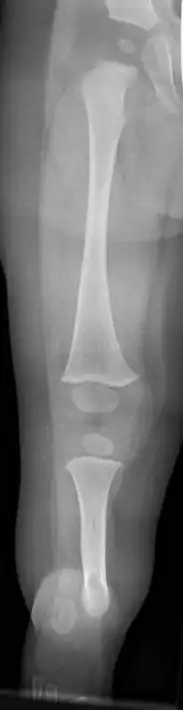

X-ray image of fibular hemimelia type II (fibula completely absent)

Fibular hemimelia or longitudinal fibular deficiency is "the congenital absence of the fibula and it is the most common congenital absence of long bone of the extremities."[1][2] It is the shortening of the fibula at birth, or the complete lack thereof. Fibular hemimelia often causes severe knee instability due to deficiencies of the ligaments. Severe forms of fibula hemimelia can result in a malformed ankle with limited motion and stability. Fusion or absence of two or more toes are also common.[3] In humans, the disorder can be noted by ultrasound in utero to prepare for amputation after birth or complex bone lengthening surgery. The amputation usually takes place at six months with removal of portions of the legs to prepare them for prosthetic use. The other treatments, which include repeated corrective osteotomies and leg-lengthening surgery (Ilizarov apparatus), are costly and associated with residual deformity.[4]

• A fibrous band instead of the fibula

• Short deformed leg

• Absence of the lateral part of the ankle joint (due to absence of the distal end of the fibula), and what is left is unstable; the foot has an equinovalgus deformity

• Possible absence of part of the foot requiring surgical intervention to bring the foot into normal function, or amputation.

• Possible absence of one or two toes on the foot

• Possible conjoined toes or metatarsals